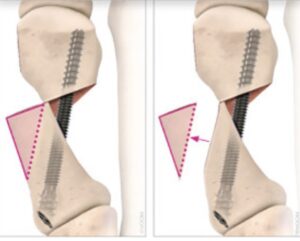

Some surgeons now want to do minimal incision bunion surgery with hideous screws. They want to TRY and do minimal incision surgery. So they use these large screws to shift the bone all the way to correct the bunion. This will result in a blown out metatarsal with severe complications. Why would you want to have this done to you? This can also result in pseudo bunions.

The pseudo bunion that results is at the yellow arrow above. These type of screws can cause a blowout metatarsal.

Stay away from surgeons that profess to do minimal incision surgery using these types of screws. They can be extremely detrimental to you.